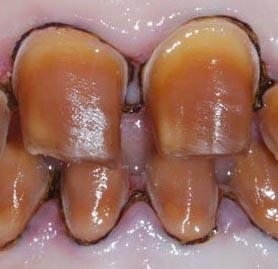

四环素牙是一种由四环素族药物引起的色素牙,是四环毒进入人体后在牙齿、骨骼等部分沉积造成的,会影响到牙釉质的生成。四环素牙虽然不会影响到健康,但是极不美观,只能通过美容的手段来改善。

1、牙体呈黄色:呈现明亮的黄色,以后逐渐有黄色变成棕褐色或深灰色;

2、前牙比后牙着色明显:乳牙着色比恒牙明显,因为乳牙的釉质比较薄,比较透明,不容易遮盖牙本质中四环素结合物的颜色;

3、牙着色程度与四环素的种类、剂量和给药次数有关。